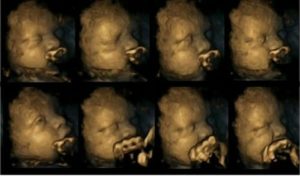

↓通常時の胎児のエコー画像です。

スヤスヤ寝ているように見えますね。